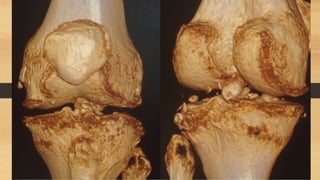

3-Lesiones multiligamentarias

asociadas a fracturas de tibia o

fémur

Clasificación de laslesiones multiligamentarias: 1-Lesiones multiligamentarias sin afectación ósea 2-Lesiones multiligamentarias con avulsiones oseas (no las de espinas tibiales) 3-Lesiones multiligamentarias asociadas a fracturas de platillo tibial

3-Lesiones multiligamentarias asociadas afracturas de tibia o fémur